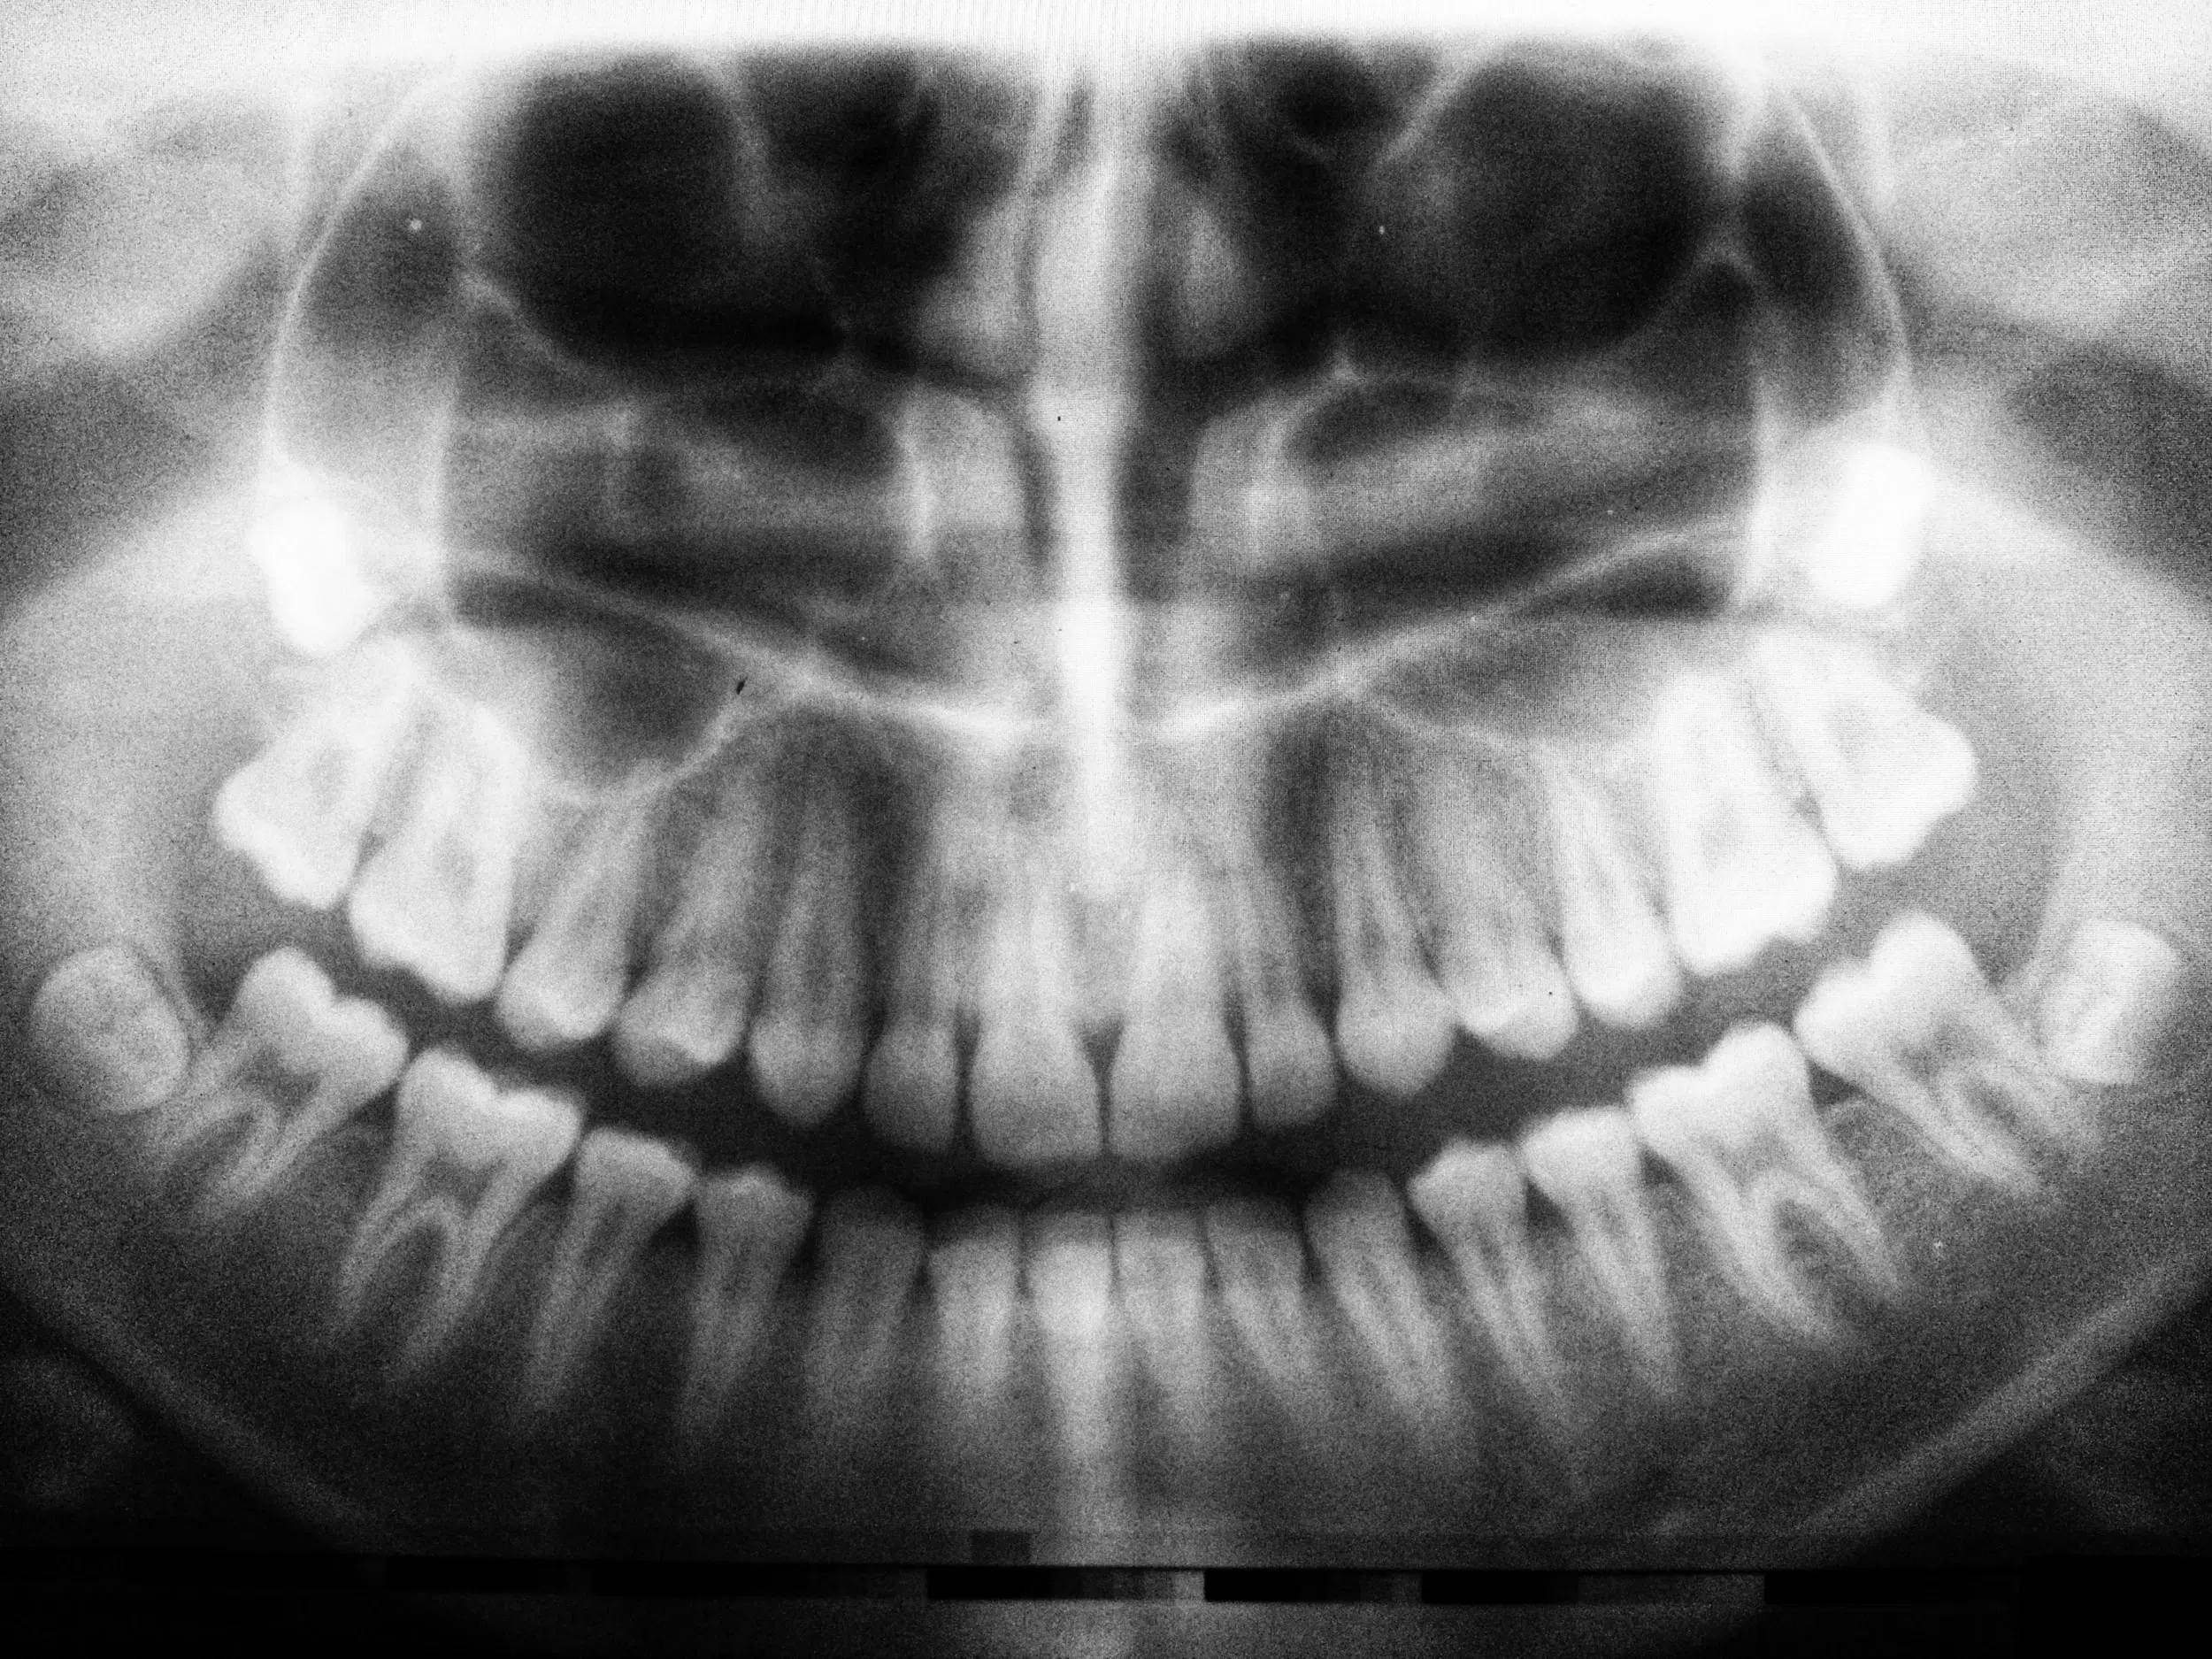

Diş Röntgeni: Çene kemiği başta olmak üzere, dişler ve ağızın destekleyici dokuları hakkında çok fazla detay verir.